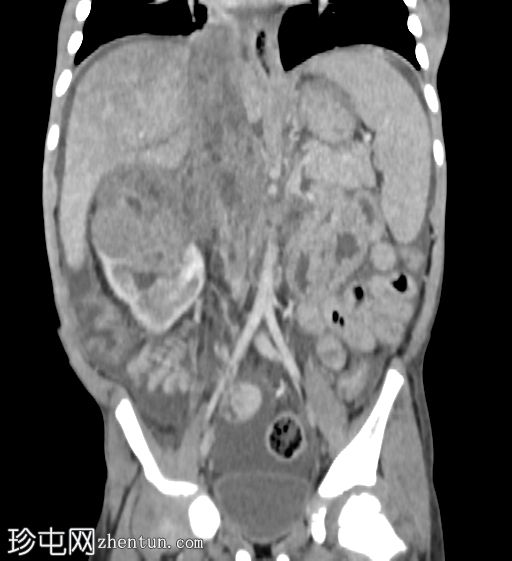

冠状位增强扫描(门静脉期)

右肾极间区可见一巨大异质性肿块,伴坏死区域。

病灶延伸至扩张的右肾静脉、右下腔静脉和右心房。

轻至中度腹水。

可见亚厘米级腹主动脉旁淋巴结。

右侧少量胸腔积液,右下叶可见一小块强化胸膜下结节。

影像学特征提示右肾母细胞瘤(Wilms瘤),伴肿瘤血栓形成至下腔静脉和右心房。